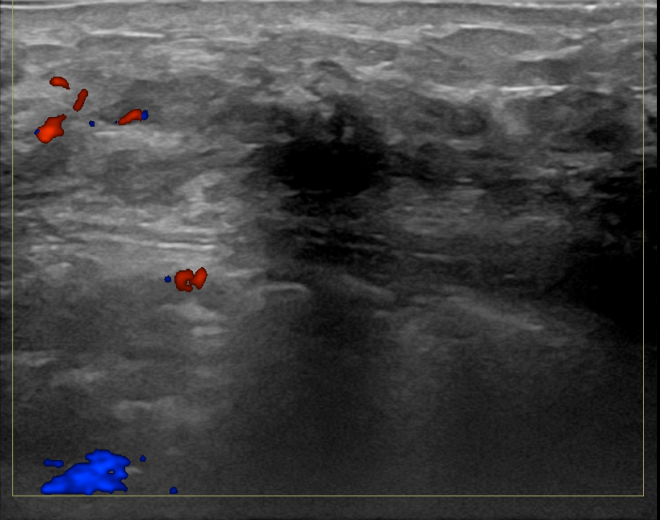

상기환자는 만져지는 멍울로 내원하신 80대초반

여성분으로 의심스러운 좌측혹 조직검사 시행해 침윤성암으로 진단되었습니다